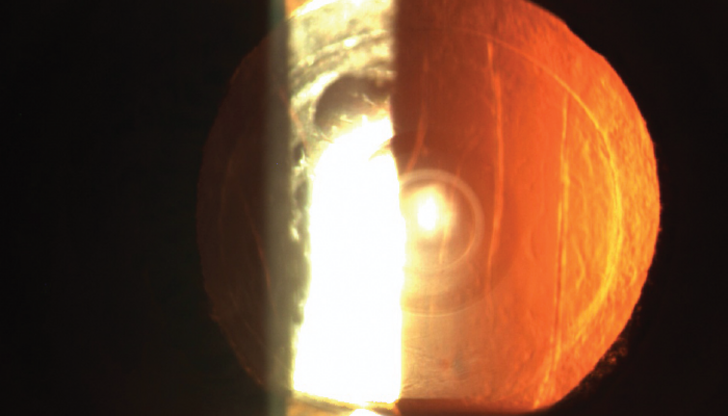

Premium lens cataract surgeries have transformed vision correction for millions globally, yet complications such as glare, halos, and blurry vision can leave some patients disappointed. Dr. Arun C. Gulani, a world-renowned eye surgeon, offers a groundbreaking, non-invasive approach to addressing these challenges by optimizing the cornea to work in harmony with the implanted lens. Learn how this innovative solution restores vision and exceeds patient expectations, all without going back under the knife.

Dr. Gulani’s method focuses on corneal optimization rather than invasive lens replacement, providing a non-surgical, effective solution for post-surgery vision complications.

Premium lens implants are just one ingredient in the overall “vision recipe.” By precisely reshaping the cornea to align with the lens, Dr. Gulani restores clarity while maintaining the integrity of the original surgery.